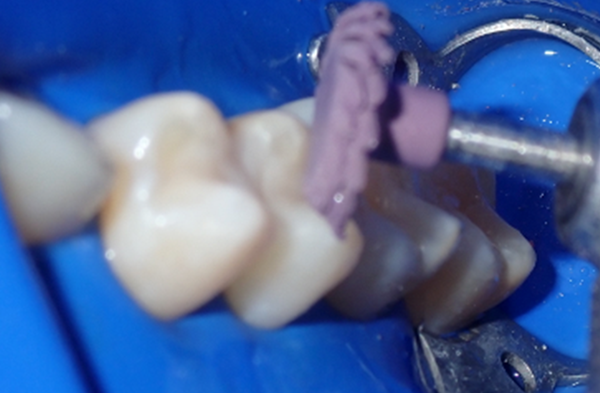

After removing the matrix system, the contacts were carefully verified using floss to ensure proper interproximal alignment. Occlusion was then assessed with articulating paper to confirm accurate bite relationships. Margins were refined using fine-grit diamond burs and carbide finishing burs to enhance precision and smooth transitions. A final polish was achieved through a multi-step polishing system designed to deliver optimal smoothness and luster. This polishing protocol included the use of Rally Polishers (Garrison Dental), A.S.A.P. Polishers (Clinician's Choice), and composite polishing paste for a high-quality, esthetic finish (Fig. 8-11).

FIG. 8

FIG. 9

FIG. 10

FIG. 11